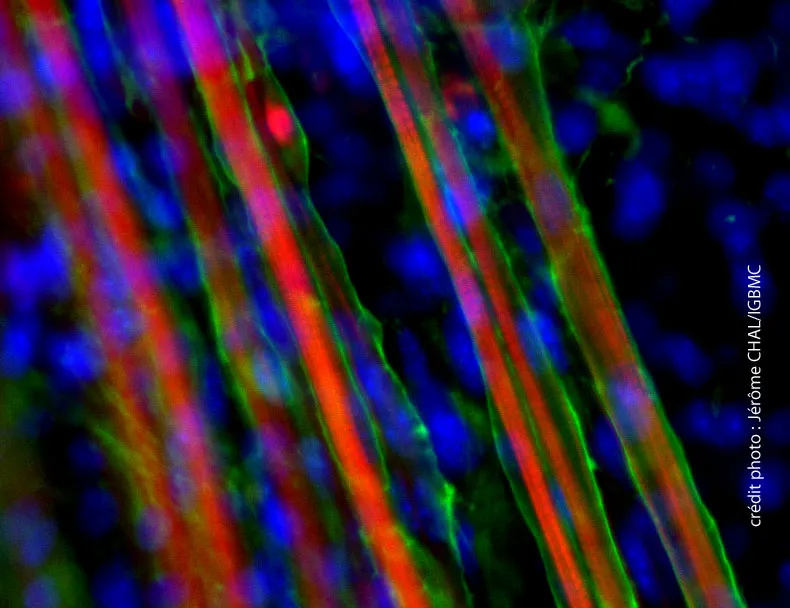

Une méthode pour obtenir des fibres musculaires et des cellules souches satellites à partir de cellules souches embryonnaires et iPS vient d’être publiée dans Nature Biotechnology (édition print du 8 septembre 2015).

Une méthode pour obtenir des fibres musculaires et des cellules souches satellites à partir de cellules souches embryonnaires a été mise au point par une équipe soutenue par l’AFM-Téléthon.